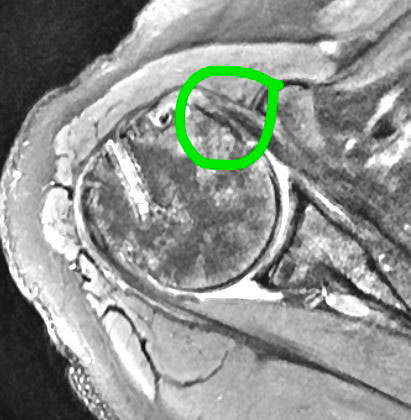

Subscapularis Tendon Tear

Subscapularis tendon tear is on the left with the healed repair visible on the right.